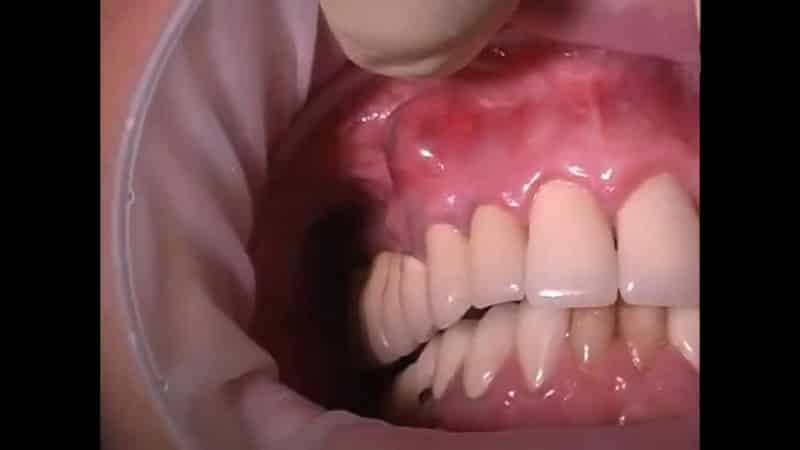

Аутоиммунное заболевание — вирусная пузырчатка также сопровождается образованием волдырей на деснах и по всему телу. У детей пузырьки часто появляются после перенесенных заболеваний, таких как корь, ветрянка, скарлатина и другие детские болезни. В некоторых случаях на десне может образоваться кровяной пузырь: его причина может заключаться в механической травме, которая не представляет серьезной угрозы для здоровья и со временем проходит. В любом случае рекомендуется обратиться за консультацией к врачу.

Существует также ряд заболеваний, которые часто сопровождаются образованием прыщей. Невылеченный пульпит или плохо запломбированные каналы могут привести к образованию кисты в верхней части зубного корня — гнойной капсулы размером до трех сантиметров. Симптомами являются увеличение десны, покраснение и отек. Это происходит, когда содержимое переполнено гноем и ищет выход, образуя свищ.

Пузырь на десне может вызывать беспокойство у многих пациентов, и врачи отмечают, что это явление требует внимательного подхода. В большинстве случаев такие образования являются результатом воспалительных процессов, например, гингивита или пародонтита. Врачи подчеркивают, что пузырь может содержать гной, что указывает на наличие инфекции. Важно не игнорировать симптомы, так как запущенные случаи могут привести к более серьезным заболеваниям, включая потерю зубов. Специалисты рекомендуют обратиться к стоматологу для диагностики и назначения соответствующего лечения. Кроме того, поддержание гигиены полости рта и регулярные осмотры у врача помогут предотвратить возникновение подобных проблем в будущем.